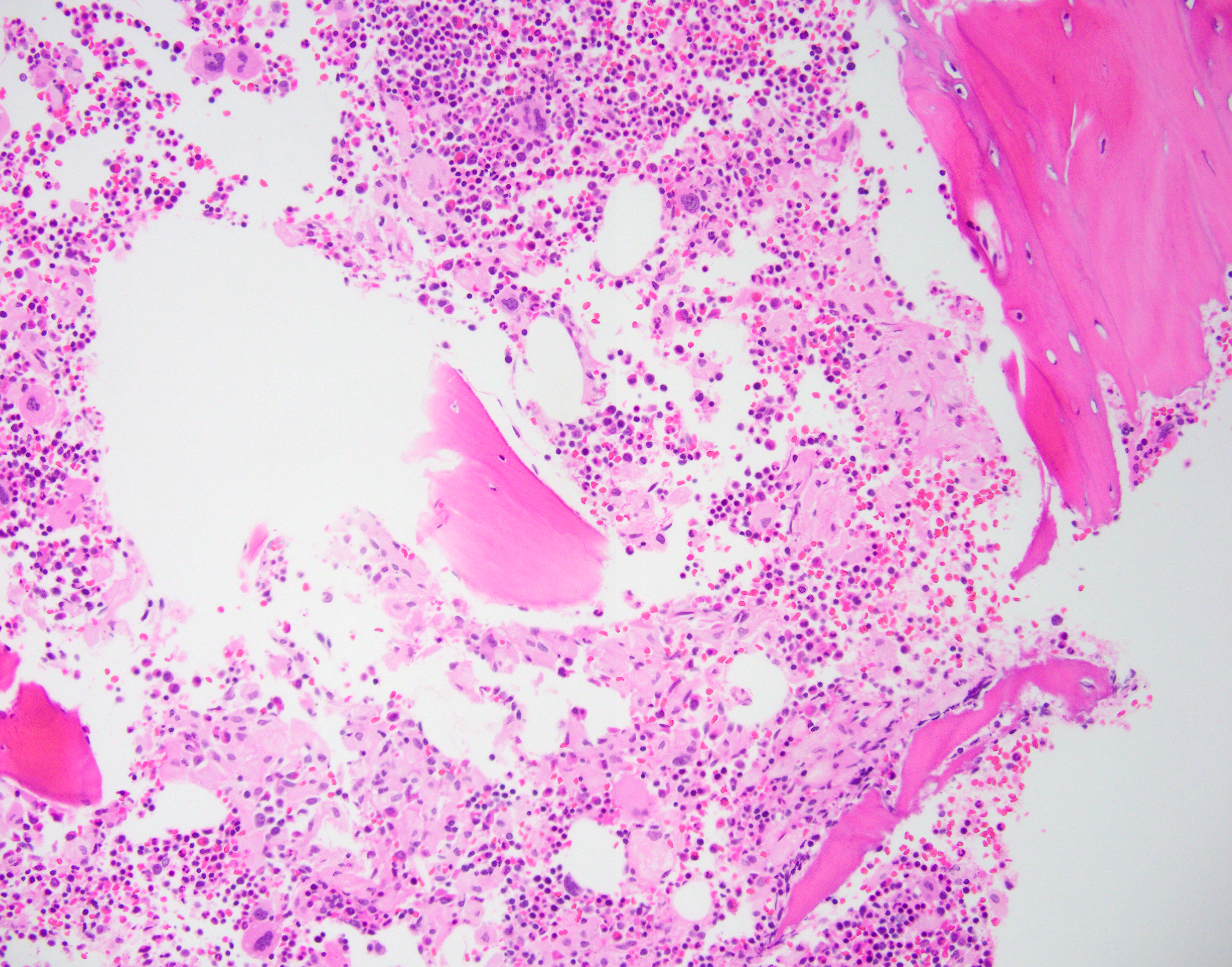

Microscopic description

Small focal accumulations or diffuse replacement by ovoid histiocytes 20 - 90 microns, with abundant, finely fibrillar, pale blue gray cytoplasm that is crinkled or wrinkled paper-like

Small nucleus with coarse chromatin and indistinct nucleolus

Increase in reticulin fibers